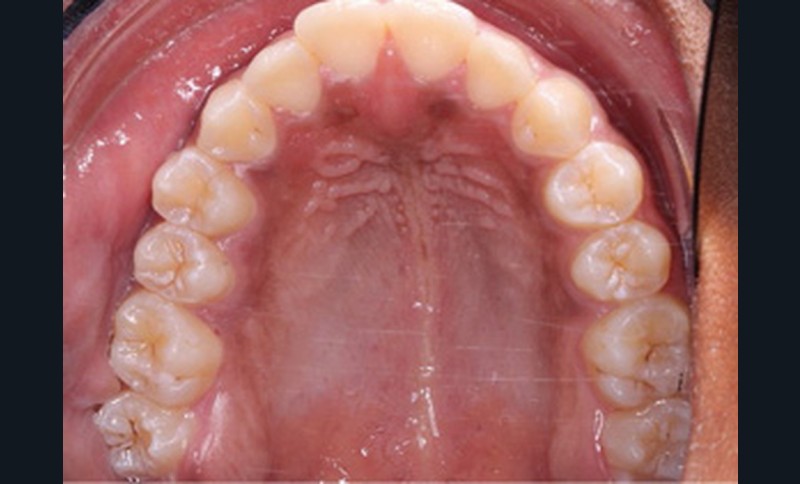

L’arcade maxillaire est en V et la voûte palatine profonde. L’arcade mandibulaire a une forme en U (non-concordance des formes d’arcade) et présente des malpositions des dents cuspidées. La médiane mandibulaire est décalée à gauche de 2 mm ; le recouvrement antérieur est de 2 mm ; les molaires sont en classe III avec un surplomb inversé.